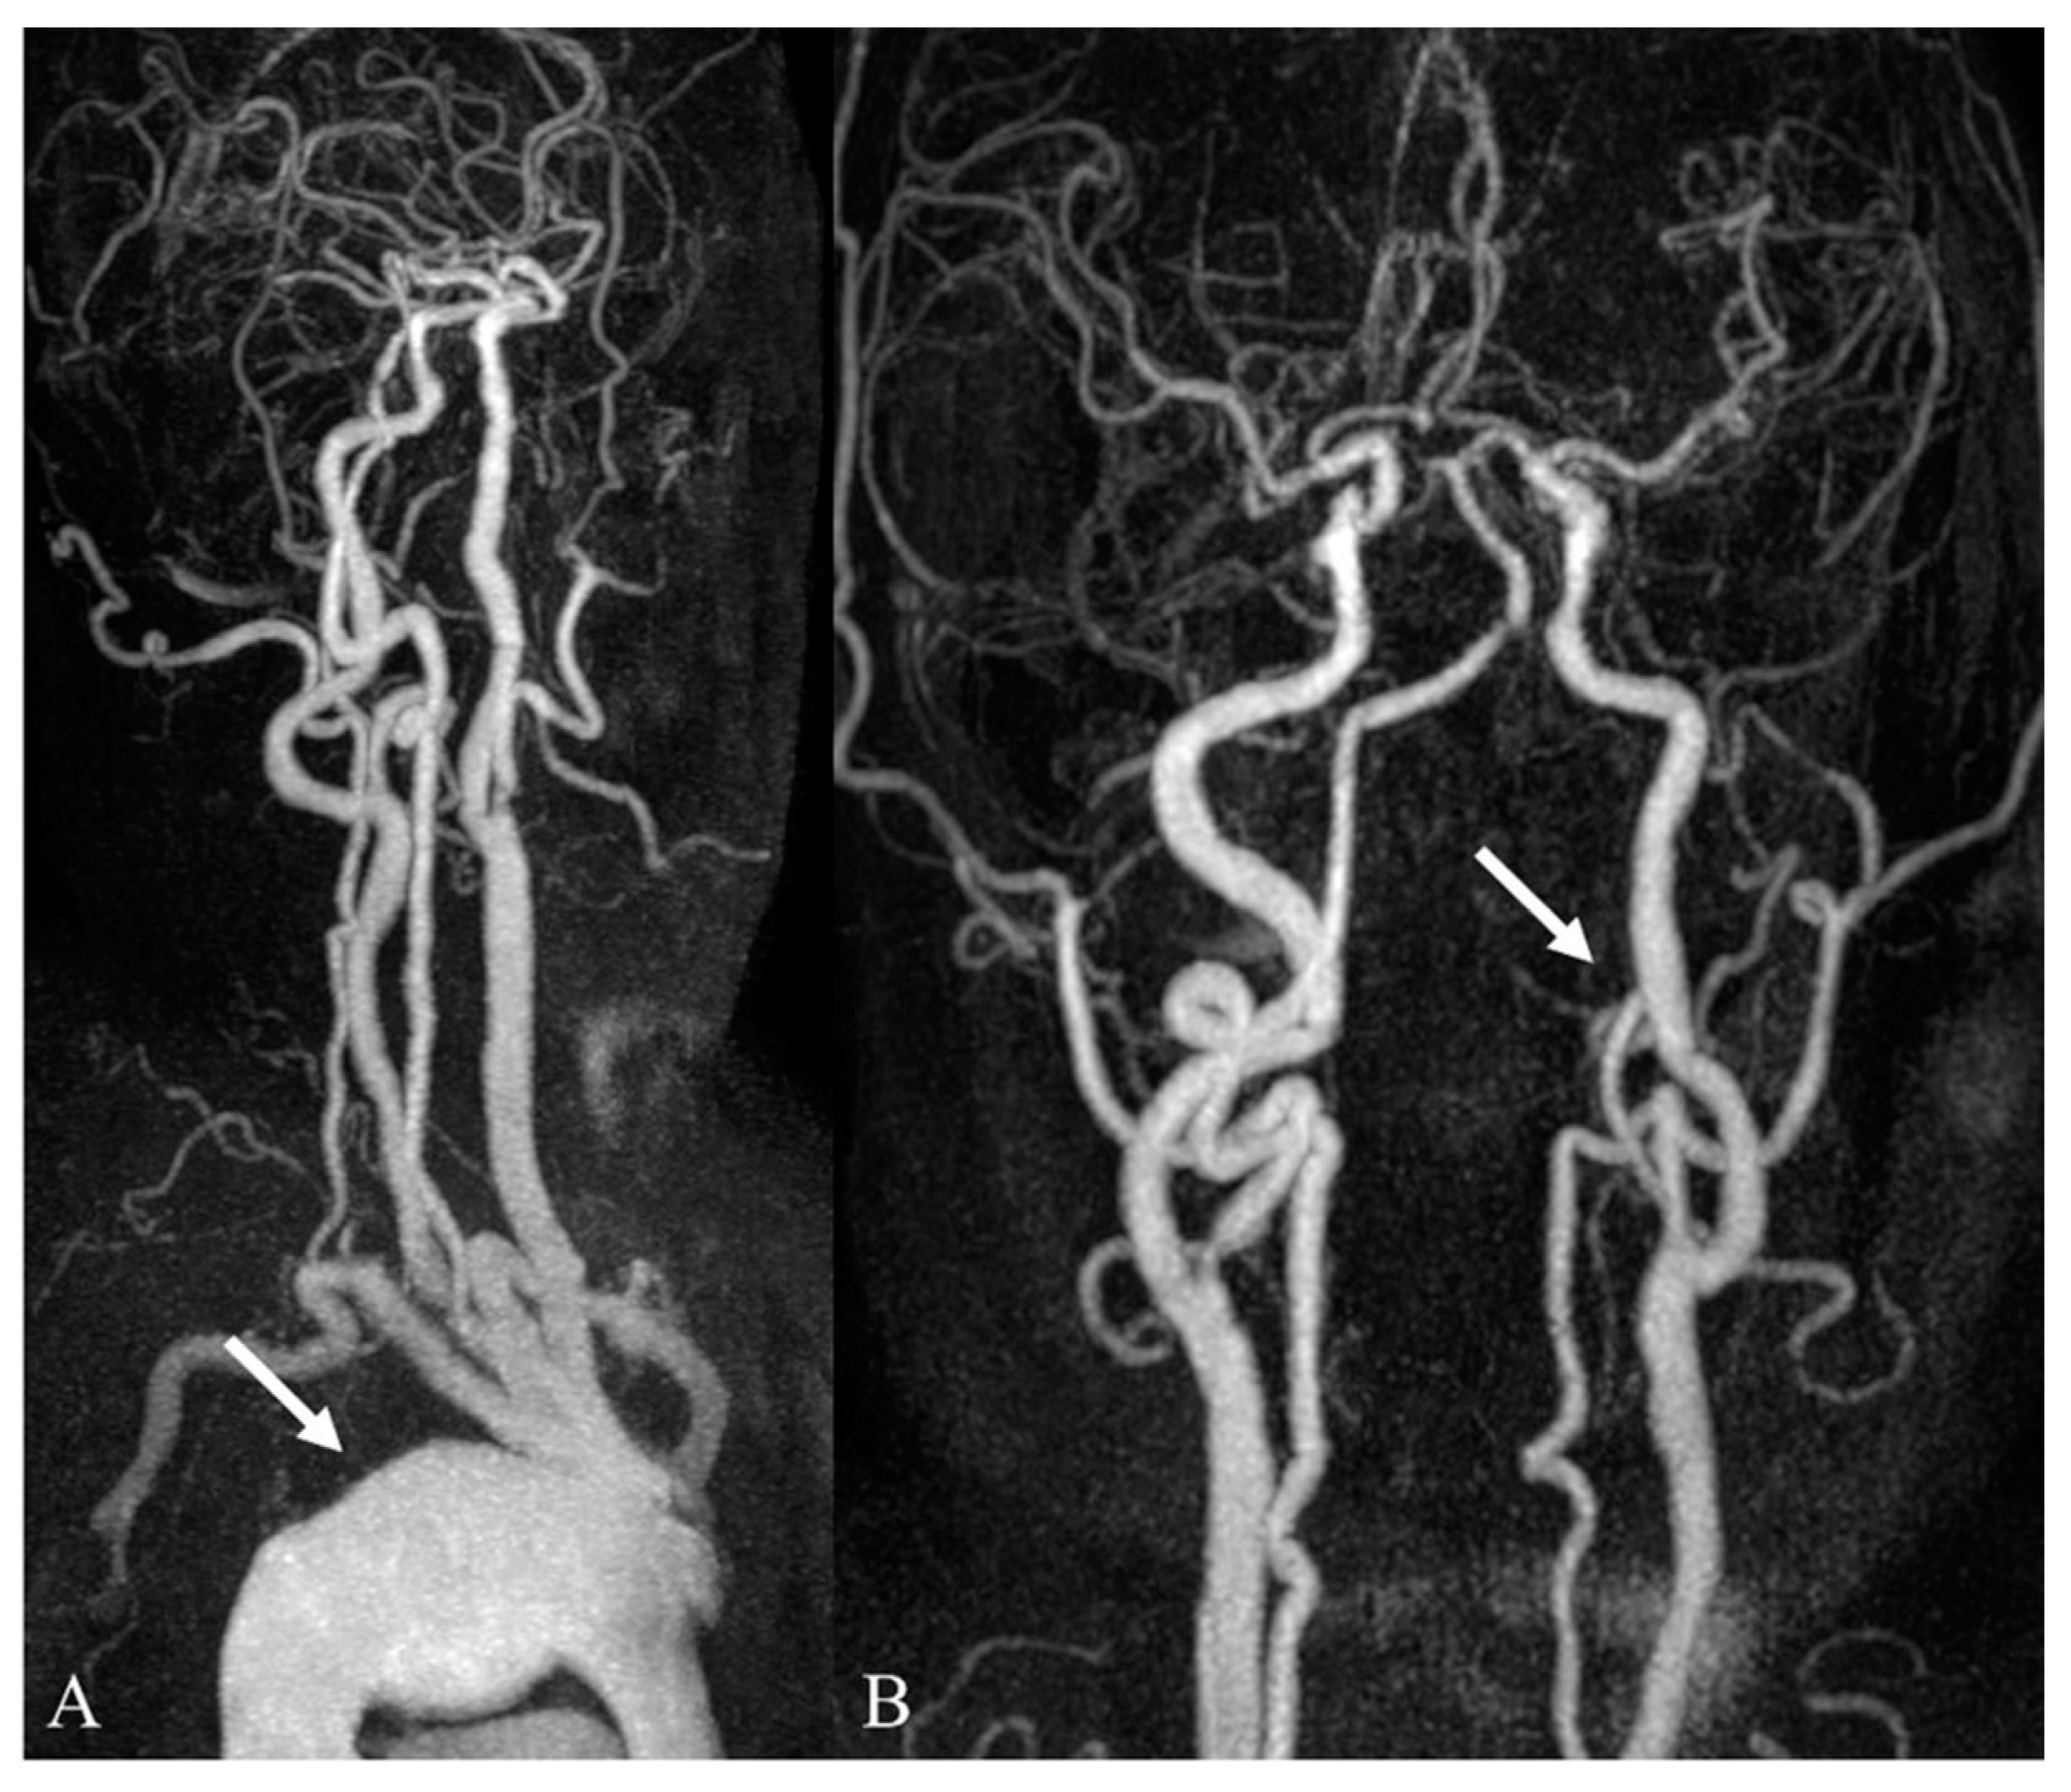

3.2. Incidental Aortic Arch Abnormalities on Contrast-Enhanced Neck MR Angiography